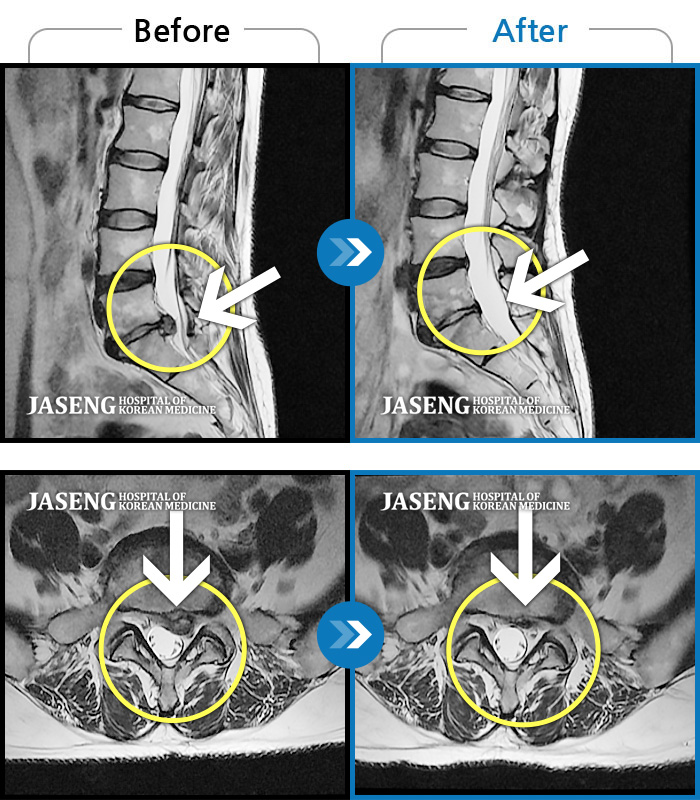

MRI 치료사례

허리 및 좌측 하지 통증